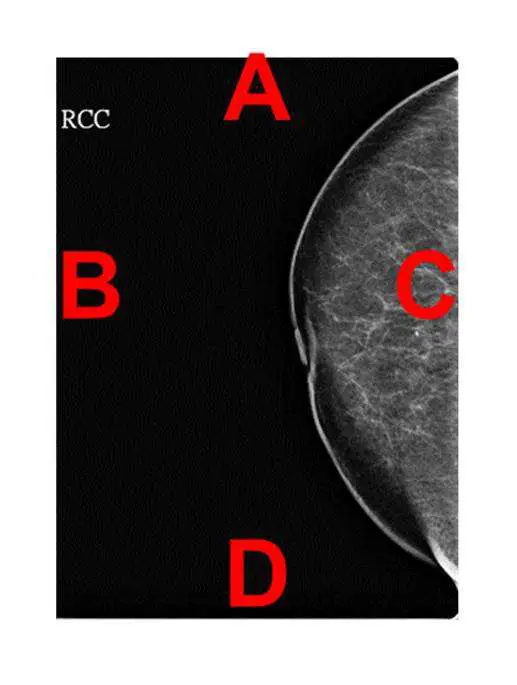

X光乳房攝影的 craniocaudal view ,如下圖,若病人擺位許可,陰極應擺放在那一側較為適當? 圖片

圖片顯示一張右側頭尾位(RCC)乳房攝影影像,並以紅色字母標示四個方位:

• A:影像上方(圖框頂端)

• B:影像左側(外側 / 腋下側)

• C:影像右側(內側 / 胸骨側,即胸壁方向)—乳房實質組織主要分佈於此側

• D:影像下方(圖框底端)

根據乳房攝影標準顯示慣例,右側乳房影像以乳頭朝左、外側在左、內側在右的方式呈現。因此:

• C 側(右側)= 內側 = 胸壁側(較厚、組織較緻密)

• B 側(左側)= 外側 = 乳頭側(較薄)